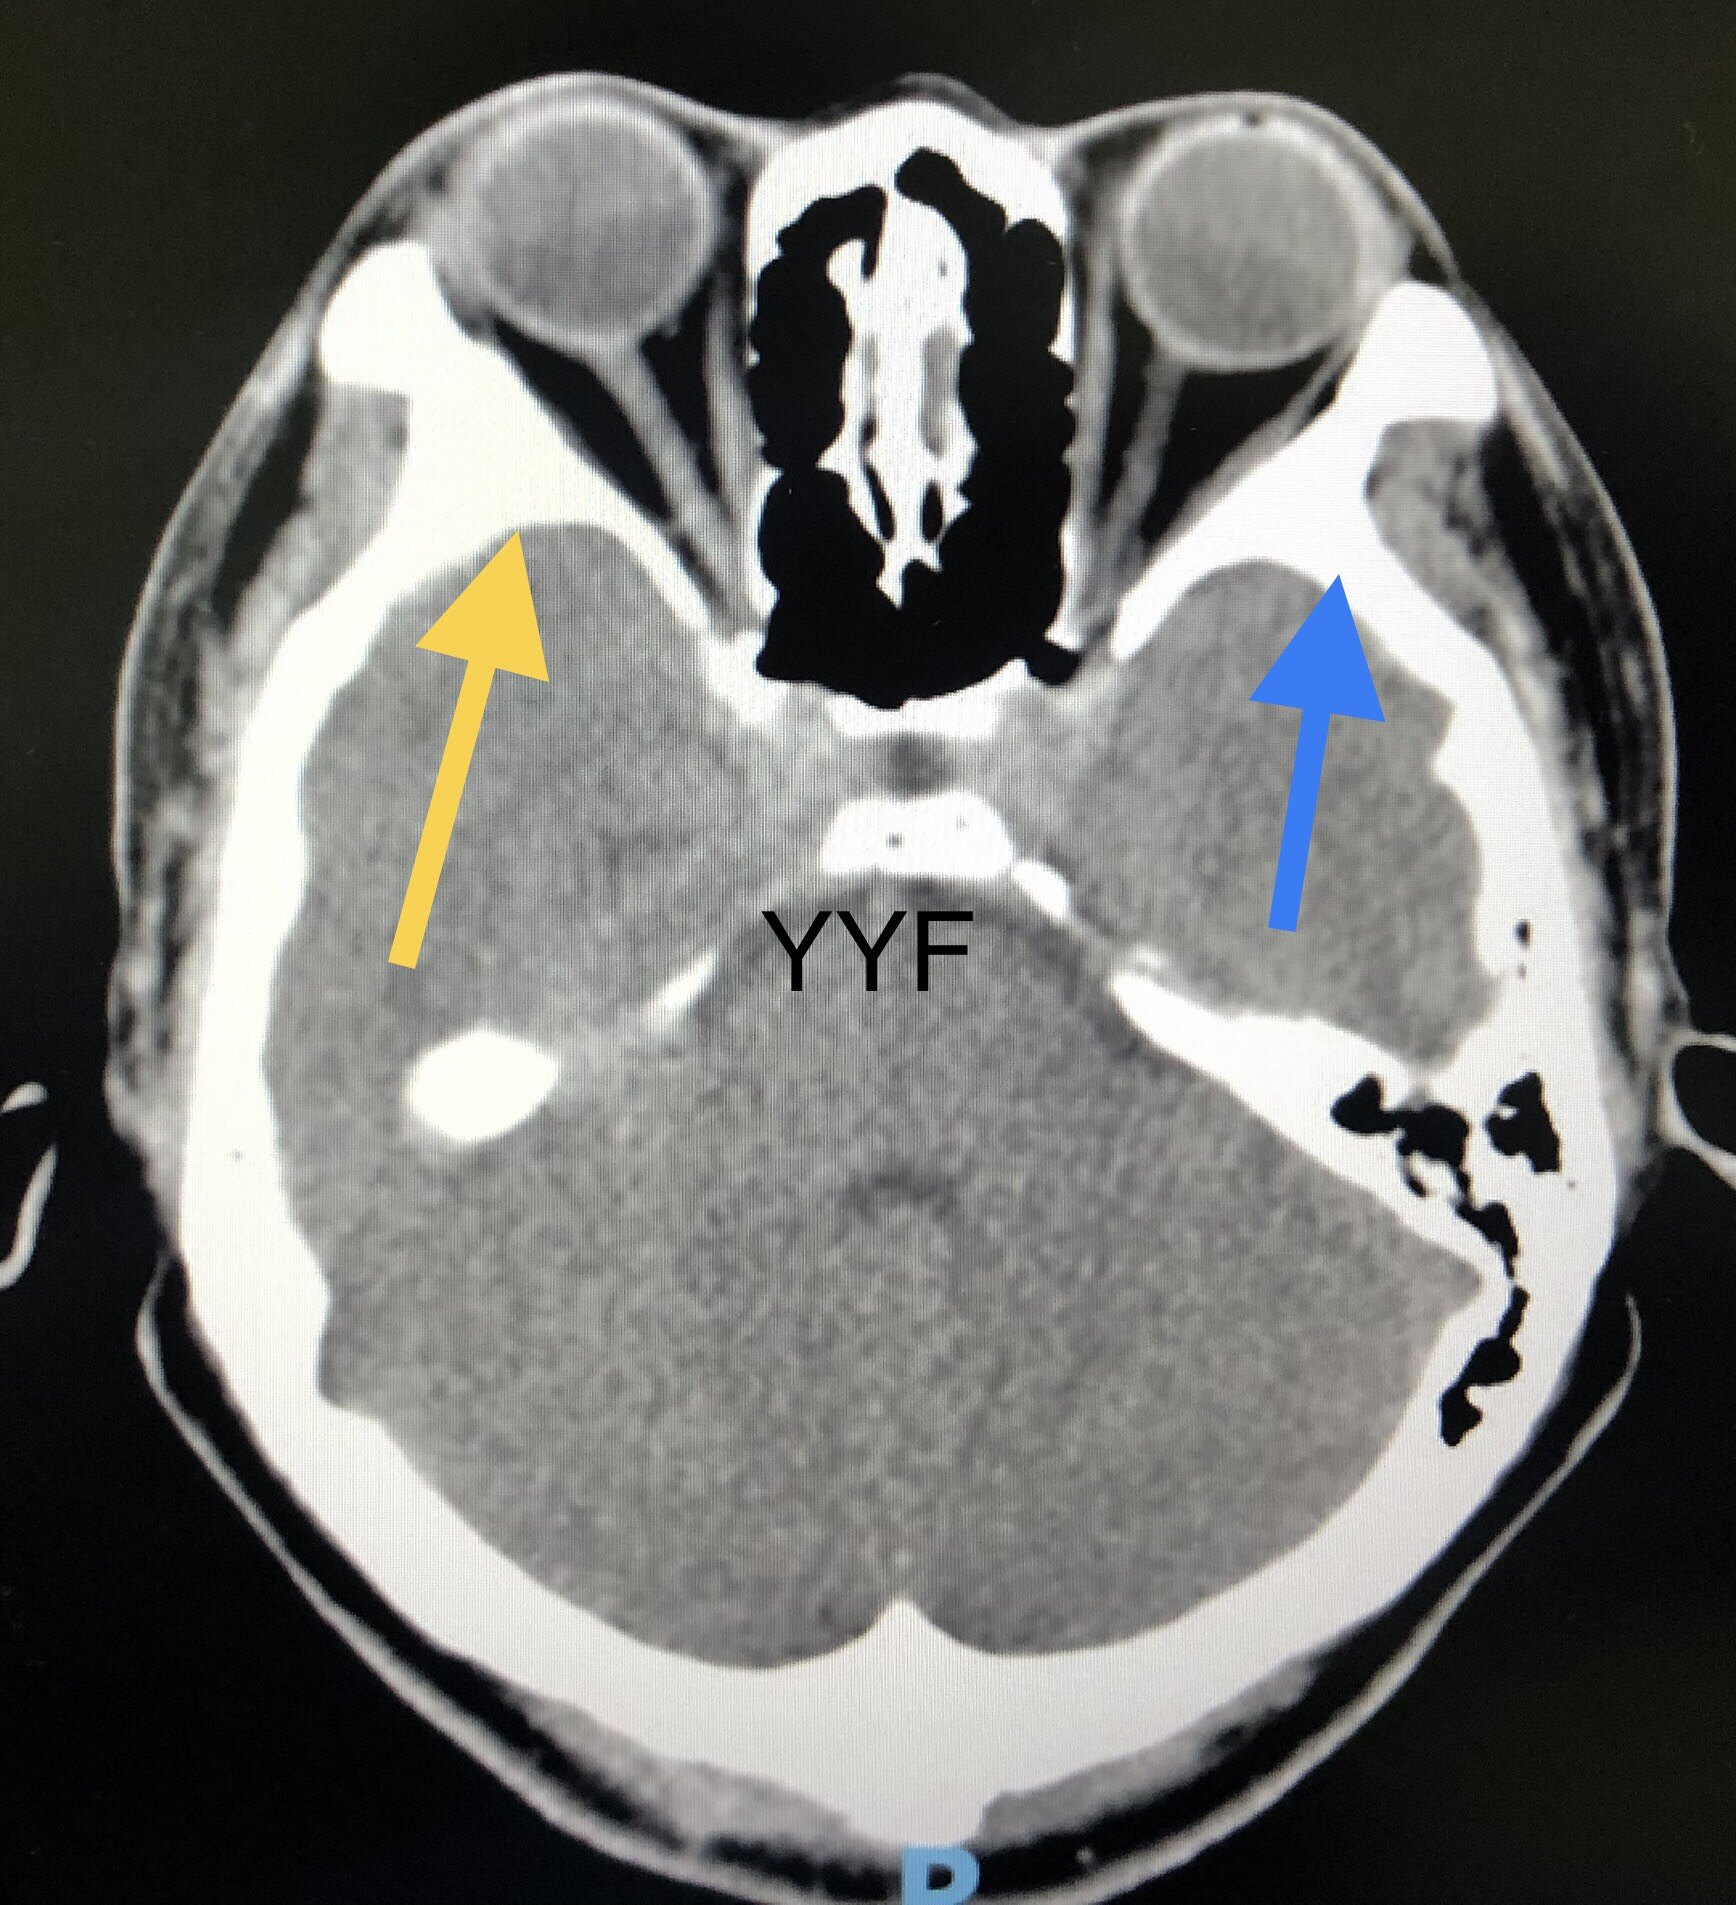

本例患者,对比双侧眼眶,可见右眼外上方骨壁增厚,骨性结构内有低信号病灶,

骨质增厚尚可,黄色箭头为增厚处